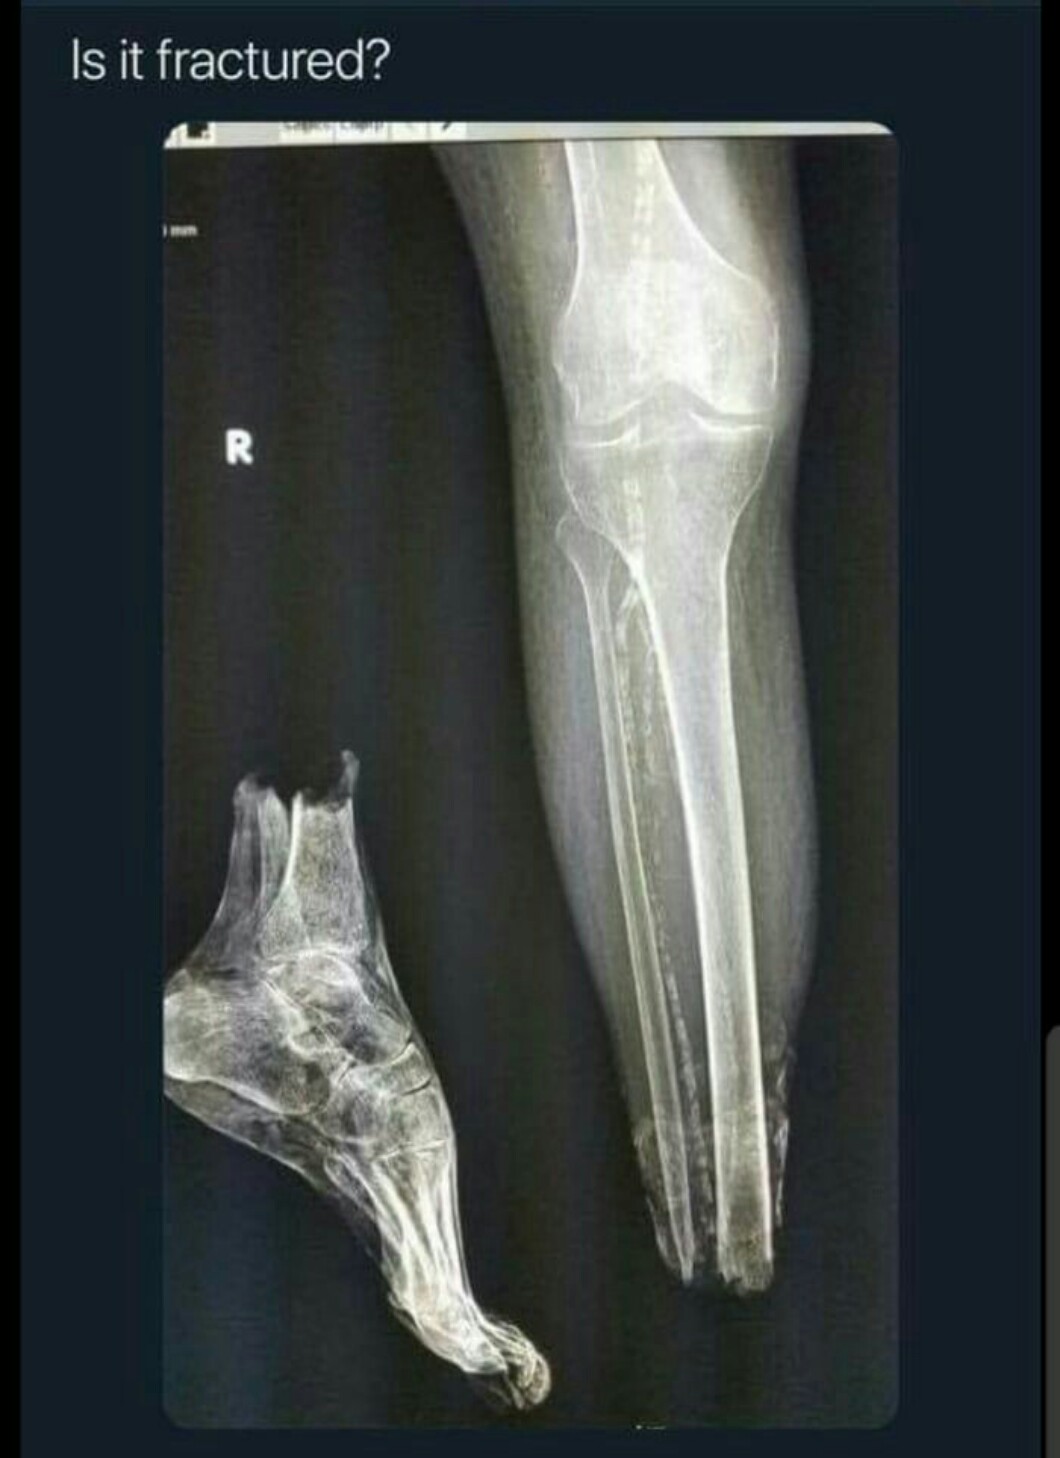

AUTOR•Gdy nadepniesz na klocka lego